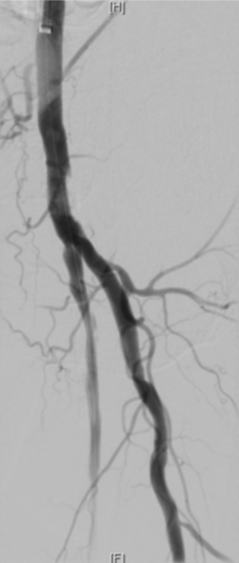

CTA:左侧股总动脉高钙化性偏心性严重狭窄病变,左股浅动脉及腘动脉全程弥漫性钙化病变,节段性狭窄,股浅动脉远段至腘动脉P1段完全闭塞,左侧胫前动脉至足背动脉闭塞

图为:术中造影评估 髂股段

根据PACSS 透视/DSA下钙化分级属于PACSS Grade 4C